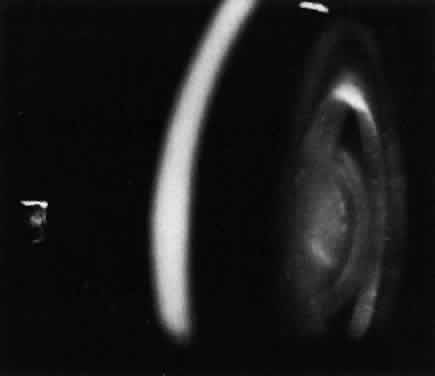

Corneal clouding (Fig. 10), hyperopic astigmatism, and a mild retinopathy with surface-wrinkling maculopathy (Fig. 11) appear to be the constant ocular triad.75 Some patients have retinal vascular tortuosity, optic nerve head swelling (Fig. 12), visual field defects, and abnormalities in color vision. Visual complaints are uncommon.

Fig. 12. Optic nerve head swelling in a patient with mucolipidosis III. (Traboulsi E, Maumenee I: Ophthalmologic findings in mucolipidosis III. Am J Ophthalmol 102:529, 1986)